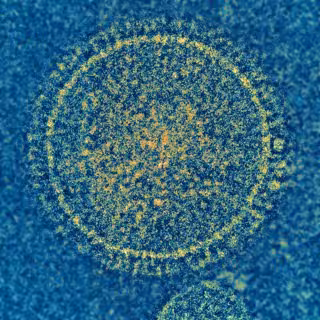

Virus sincitial respiratorio

NIAID

El trabajo, publicado en la revista 'EMBO Molecular Medicine', podría cambiar el tratamiento del virus respiratorio sincitial (VRS) y el metaneumovirus (MNV) humano, dos virus muy parecidos tanto clínicamente como biológicamente, que son la causa principal a nivel mundial de la mayoría de las infecciones respiratorias graves (principalmente bronquiolitis y neumonías), que ocurren preferentemente en los meses de invierno, en niños menores de cinco años y sobre todo en los dos primeros años de vida.